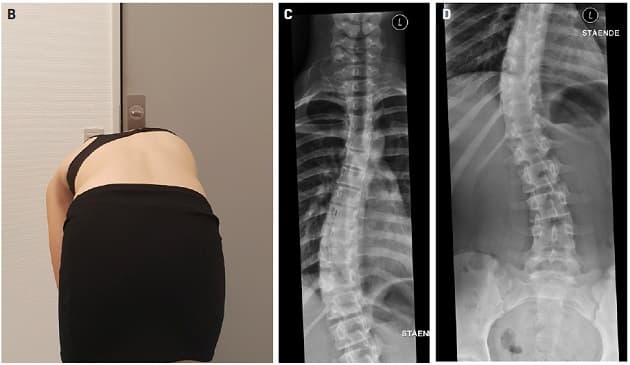

©. Pige med S-formet torakolumbal skoliose. B. Klinisk billede med patienten i foroverbøjet stilling. C. Den torakale del af skoliosen. D. Den lumbale del af skoliosen.

Blandt de strukturelle skolioser er adolescent idiopatisk skoliose den hyppigste med en prævalens på 2-3%. Statusartiklen af Christian Wong fokuserer på skolioserelaterede smerter, som har vist sig at forekomme hyppigere end tidligere antaget. Forfatteren konkluderer, at behandlingen først og fremmest omfatter smertelindring med paracetamol og rygstyrkende træning, men omtaler også forsøg med muskelrelakserende injektionsbehandling med botulinumtoksin.